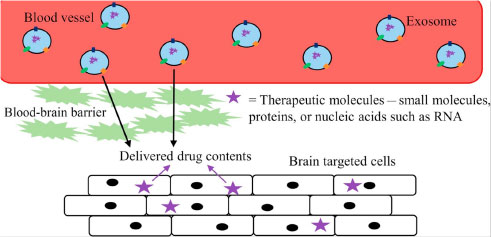

Their small size gives exosomes the advantage of being able to circulate more easily through the body.

它们的小尺寸使外泌体具有能够更容易地在体内循环的优势。

When exosomes are delivered directly into an affected joint, they start signaling to the cells to return to healthy function.

当外泌体直接输送到受影响的关节时,它们开始向细胞发出信号以恢复健康功能。

They send proteins into the walls of the cells telling the cells how to regulate themselves.

它们将蛋白质送入细胞壁,告诉细胞如何自我调节。